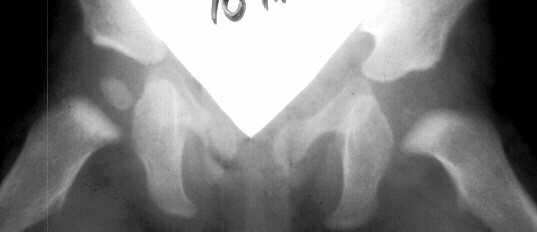

Trochanteric

overgrowth is more of a problem with damage to the central physis.

Severe

AVN of the femoral head leads to femoral neck shortness and coxa

magna only because the epiphysis has been injured.

Arrest

of the medial physis also commonly occurs and leads to coxa vara.